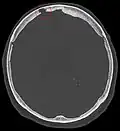

CT angiography showing an arachnoid granulation in the right transverse sinus -

Non-contrast CT scan of the head showing an arachnoid granulation